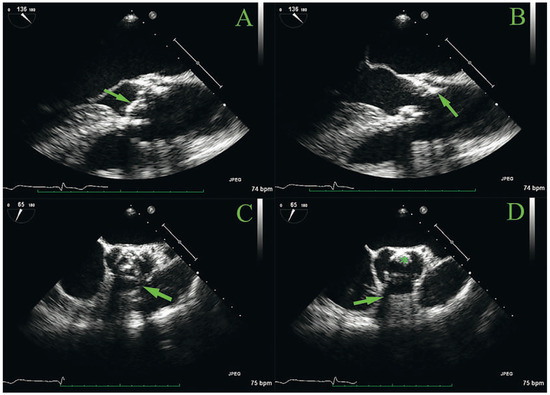

Obstructive thrombus is a rare complication of surgical valve replacement. Current guidelines recommend treatment with repeat surgery or fibrinolysis, especially in critically ill patients, despite a high risk of complication and death linked with these treatments. The treatment of haemodynamically stable patients is, [...] Read more.

Obstructive thrombus is a rare complication of surgical valve replacement. Current guidelines recommend treatment with repeat surgery or fibrinolysis, especially in critically ill patients, despite a high risk of complication and death linked with these treatments. The treatment of haemodynamically stable patients is, however, less well documented. We describe the rare case of a 40-year-old patient presenting with symptomatic but stable obstruction late after porcine bioprosthetic aortic valve replacement, who was successfully treated with oral anticoagulation. Interruption of oral anticoagulation resulted in rapid recurrence of obstruction, highlighting the importance of long-term anticoagulation in such cases. Full article

Show Figures

Figure 1